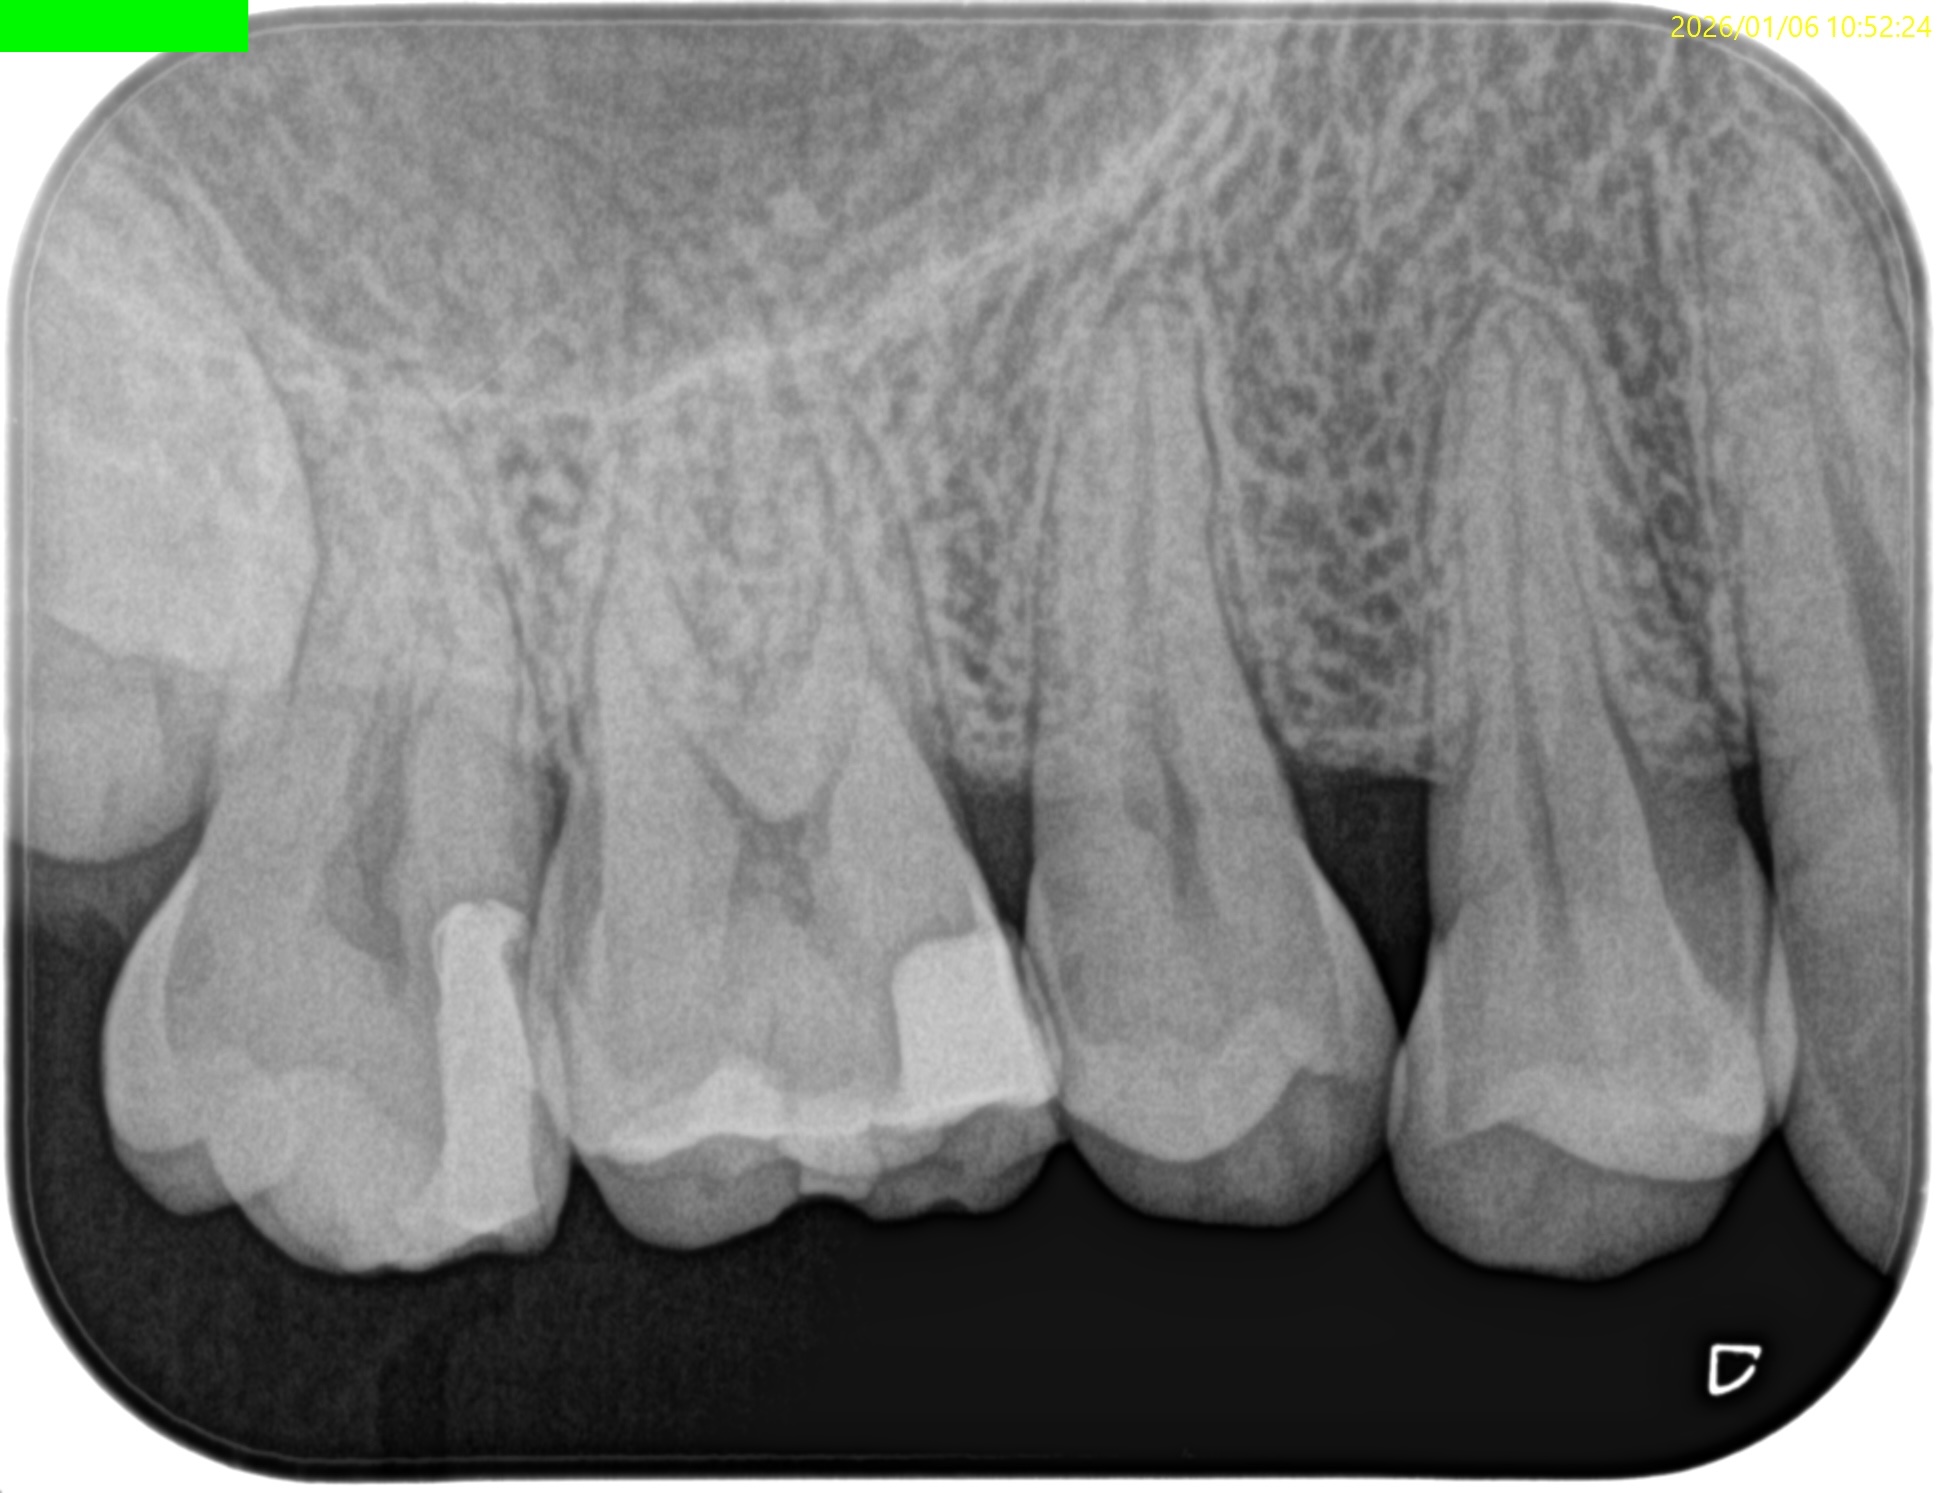

過去治療の経過観察。

1年以上前に, #14 Intentional Replantationを行っていた。

術前にSinus tractがあり、

3根管全てがここまで大きく拡大形成されており、

DBとPがつながっている。上顎第2大臼歯のような第1大臼歯で、

歯根を取り囲むように歯槽骨が溶けている。

垂直性歯根破折が疑われる。

そして、頬側の歯槽骨がほとんどない。

この治療から1.9yr経過していた。

#14 Intentional Replantation 1.9yr recall(2026.1.6)

術前のSinus tractは消失した。

PA, CBCTも撮影した。

初診時と比較した。

問題が劇的に解決していることがわかる。